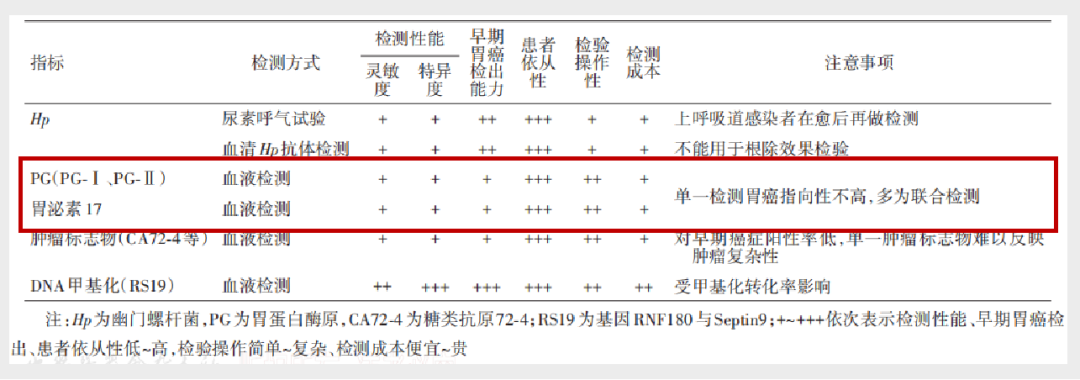

ж–°е…ұиҜҶгҖҠдёӯеӣҪж—©жңҹиғғзҷҢзӯӣжҹҘзЈЁз»ғжүӢиүә专家е…ұиҜҶгҖӢжҺўи®ЁдәҶеӨҡз§Қеёёи§Ғзҡ„ж—©жңҹиғғзҷҢзЈЁз»ғжүӢиүә�гҖӮ�гҖӮжң¬зҜҮж–Үз« еёҰдҪ дёҖиө·и§ЈиҜ»ж–°е…ұиҜҶ�пјҢ�пјҢ�пјҢпјҢзӣёиҜҶж–°е…ұиҜҶзҡ„дёүеӨ§йҮҚзӮ№йғЁеҲҶпјҡж—©жңҹиғғзҷҢзҡ„зЈЁз»ғжүӢиүәгҖҒж—©жңҹиғғзҷҢзҡ„жЈҖжҹҘж Үи®°зү©гҖҒж—©жңҹиғғзҷҢзҡ„зӯӣжҹҘжҺЁиҚҗжөҒзЁӢ�гҖӮ�гҖӮ